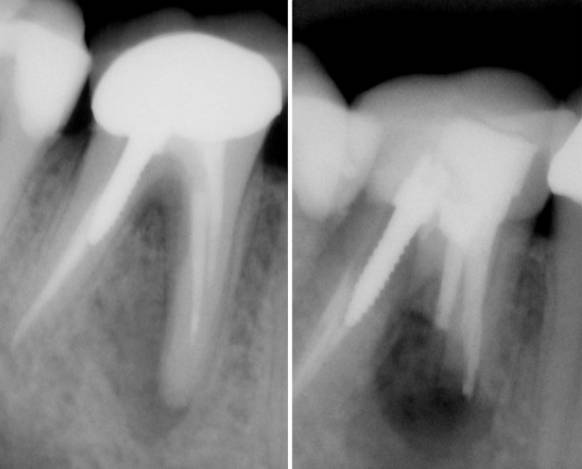

Indicamos esta microcirugía cuando, pese a una endodoncia bien realizada, persiste una lesión apical que no cede y el retratamiento ortógrado no es viable o ya ha fracasado. Es una vía conservadora para salvar el diente sin recurrir a la extracción: tratamos el problema “por la punta” de la raíz, donde se mantiene el foco.

El pronóstico empieza en el diagnóstico. Valoramos la longitud radicular remanente (necesitamos suficiente raíz para que el diente sea estable), el tamaño y la forma de la lesión, si existe poste en el conducto y la proximidad a estructuras críticas como el nervio o el seno. Cuando estas variables se alinean, la probabilidad de éxito es alta y, sobre todo, predecible.

Técnica clave

Accedemos al ápice mediante una ventana ósea precisa, resecamos aproximadamente 3 mm de la punta de la raíz y preparamos una cavidad retrógrada con ultrasonidos. Posteriormente sellamos con materiales biocerámicos (MTA/BC) y controlamos la hemostasia para mantener un campo limpio. El objetivo es doble: eliminar el foco y crear un sellado estanco que impida futuras filtraciones.

Pronóstico y alternativas

En casos bien indicados, las tasas de éxito se sitúan alrededor del 80–90%, con controles radiográficos a los 6 y 12 meses para verificar la cicatrización. Si el diseño del caso no es favorable, priorizamos el retratamiento ortógrado cuando es posible; y si el diente no ofrece garantías de longevidad, explicamos con transparencia la opción de extracción y la planificación restauradora posterior. La clave está en escoger la estrategia que te dé el mejor resultado a medio y largo plazo.